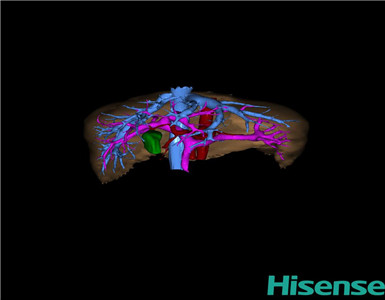

CT结果输入海信CAS系统后行3D重建及手术规划后,于2015-1-8全麻下行“肝脏肿瘤切除术”。

术前三维重建及手术方案设计:

将0.625mm双源薄层CT资料的静脉期和动脉期Dicom格式文件导入海信CAS系统。

通过调节窗宽窗位调整CT序号,对肝实质,胆囊,下腔静脉,肿瘤,肝动脉、门静脉及肝静脉等进行三维重建;系统自动计算肝脏体积。

术前三维重建:

重建图片